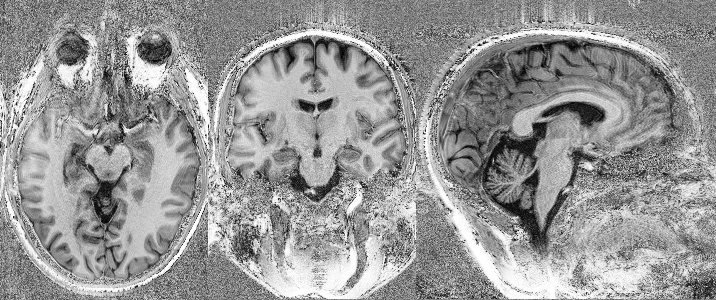

In vivo imaging of the human brain with the Iseult 11.7-T MRI scanner

Nature Methods. 2024. doi: 10.1038/s41592-024-02472-7.

First in vivo images of the human brain revealed with the Iseult 11.7T MRI scanner

Opening New Horizons With The First Human Brain In Vivo Experiments At 11.7T

Proceedings of the ISMRM 2024, Singapore, p0523.